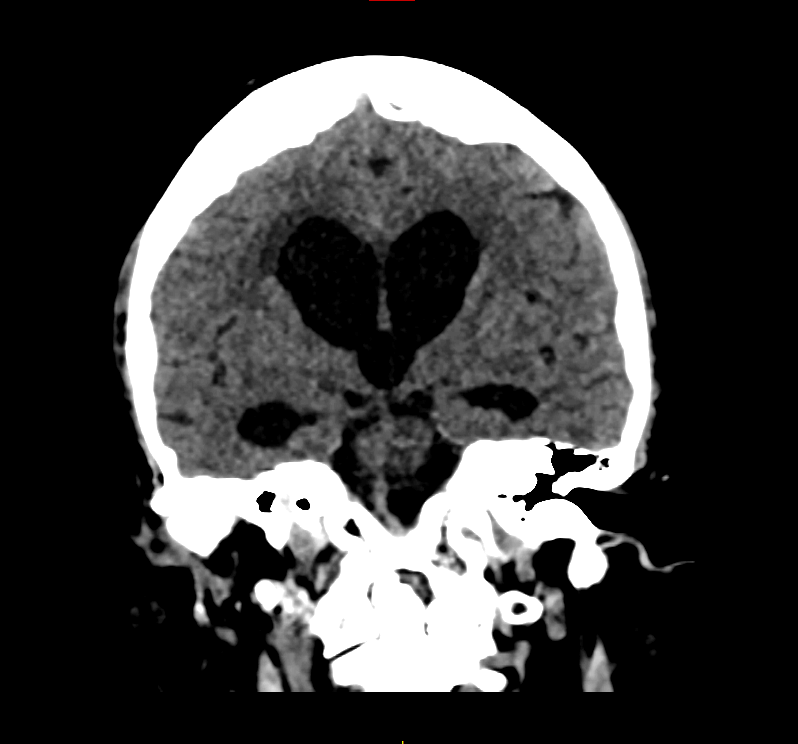

L’hydrocéphalie est définie par une augmentation du volume des ventricules cérébraux responsable de symptômes cliniques. Les ventricules cérébraux sont des cavités situées au centre du cerveau qui contiennent le liquide cérébro-spinal (LCS). Ils sont au nombre de 4,  communiquent entre eux puis le liquide circule dans les espaces autours du cerveau (espace sous arachnoïdien).

Hydrocéphalie

Figure 1. Hydrocéphalie

Ainsi, une imagerie cérébrale (IRM ou Scanner) est réalisée permettant de constater l’augmentation du volume des ventricules.